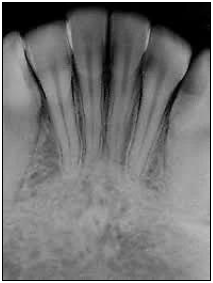

Observe a imagem a seguir.

(White & Pharoah, 2007.)

Qual é a área radiografada mostrada na figura?